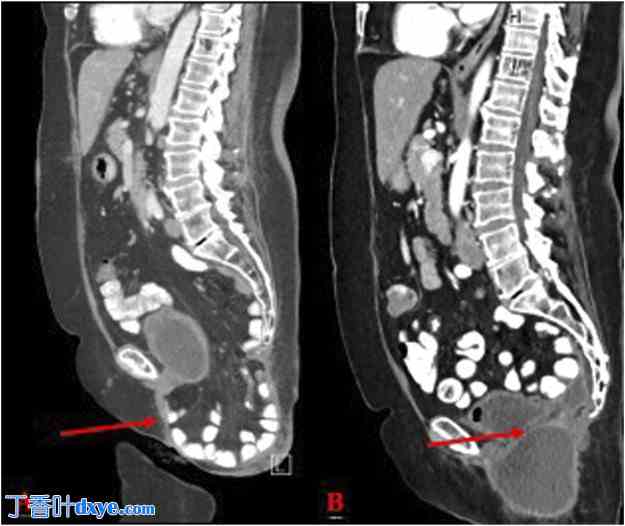

术后约一年,患者主诉会阴部疼痛性膨出,平躺时症状有所缓解,但站立或活动时症状加重。患者特别指出,她能感觉到肠子下降到疝囊内,并能手动加压疝气复位。患者进行了口服和静脉注射造影剂的CT扫描,以区分会阴疝和血清肿。影像学检查证实为会阴疝,伴有小肠和大网膜嵌顿。患者接受了诊断和治疗方案的咨询,最终选择了机器人会阴疝修补术(网片植入)(图1A)。

图1.

(A) 会阴疝术前CT扫描(红色箭头);(B) 术后一个月CT图像,显示会阴疝手术矫正;(C) 术后一年CT图像。